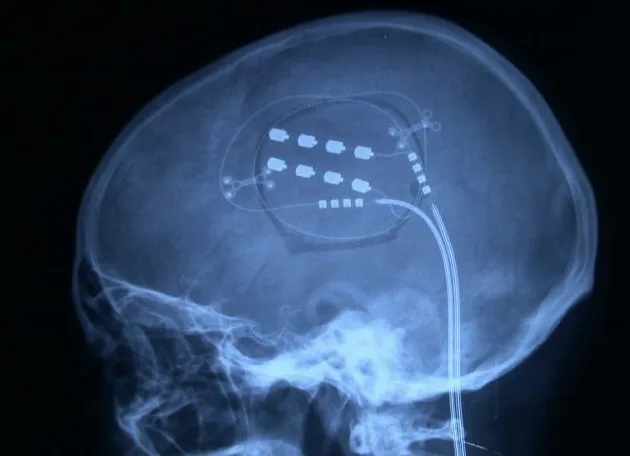

Estimulación de la corteza motora

Curiosamente, también funciona la estimulación de la corteza cerebral, específicamente de la corteza motora. Se colocan mallas de electrodos de este tipo sobre la corteza y se mantiene con una especie de marcapasos una estimulación continua.

Esta estimulación de la corteza motora va fundamentalmente dirigida a los dolores por desaferentización. Todas estas técnicas representan opciones terapéuticas que, según el tipo y localización del dolor, pueden ofrecer alivio significativo a los pacientes.